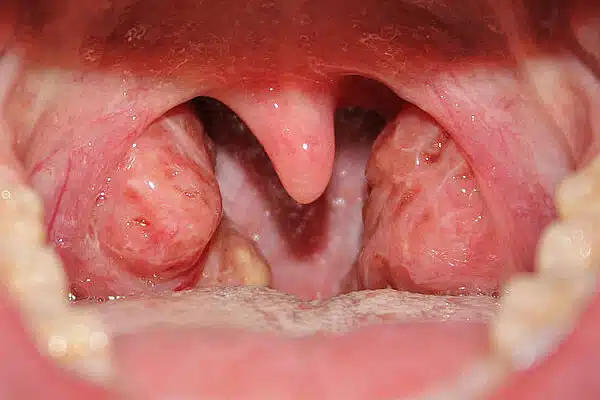

Tonsils are two clusters of tissues that are located on both sides of the throat. They are embedded at the palate (the mouth roof) side. When you eat or drink, the throat muscles push the tonsils together, therefore small particles of food may lodge in the crypts of the tonsils. These particles may lead to infection of tonsils. Adenoid is a single cluster of tissue in the nasopharynx (back of the nose) located at the pharynx.

Though tonsils keep bacteria and viruses out they can get infected themselves, as they are sometimes overwhelmed. Tonsils removal may be necessary if the child has frequent throat infections (six to seven episodes per year) that include a fever and swollen lymph nodes. Other reasons include:

- Blockage of the nose and throat

- White debris in tonsils

- Unusual enlargement or appearance